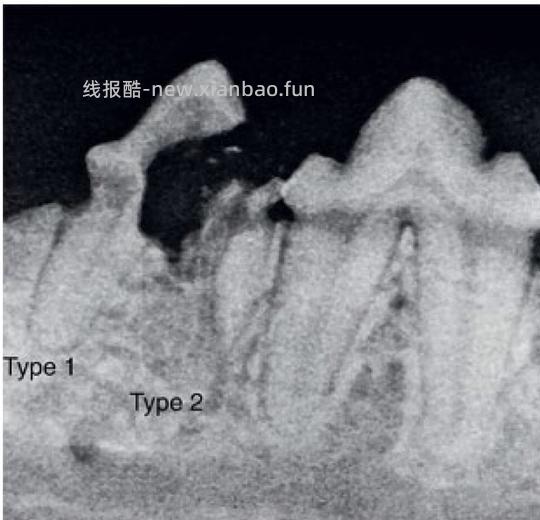

口腔内X光牙科片在诊断和确定治疗计划上起着重要作用。根据在影像学上表现出的特点,牙吸收可分为三种类型如下(图10)[1, 18]:

图*10(a)1型牙吸收(b)2型牙吸收(c)3型牙吸收[18]

Type1(T1): 对于具有1型吸收牙齿的X射线照片,该牙齿呈现局灶性or多灶性射线可透过性,其他部分则保持正常的射线不透性及正常的牙周韧带结构 - 图10(a)+图11

Type2(T2): 对于具有2型吸收的牙齿,牙周韧带间隙至少在某些区域变窄或者消失,部分牙齿的射线不透性降低 - 图10(b)+图12

Type3(T3): 3型吸收的牙齿在同一颗牙上具有1型和2型的特点,即受影响的牙齿既存在牙周韧带间隙的狭窄/丢失,也同时存在局灶性or多灶性射线可透过性和牙齿其他区域射线不透性降低 - 图10(c)+图13